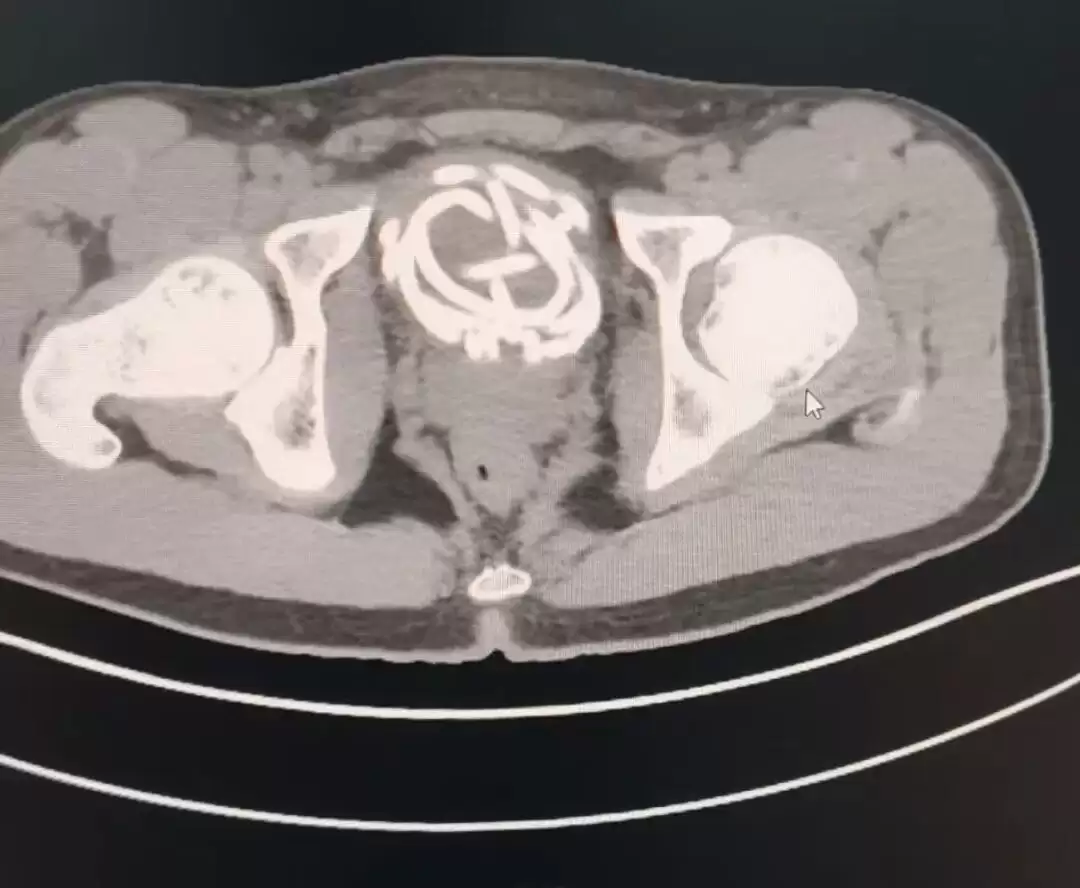

近日,扬州大学附属医院泌尿外科接诊了一名17岁高中男生,他由于好奇将跳绳的橡胶绳插入尿道,跳绳在膀胱内打结盘曲无法取出,并引发严重尿道感染,医生通过紧急手术,才胜利取出跳绳。

(患者医学影像,图源扬州大学附属医院)

据理解,这名男生因一时好奇,将橡胶跳绳插入尿道,无法取出,随后出现剧烈疼痛、排尿艰难等症状。医生立即为患者进行相关检查。检查后果显示,跳绳已经在膀胱内打结盘曲,由于滞留时间较长,患者尿道已出现严重感染并形成脓胎,假如不及时手术,或许引发更加严重的并发症。

在手术流程中,医生看到患者尿道黏膜由于异物刺激已经布满脓苔,跳绳相互缠绕,形成难以解开的死结。为最大水平降低创伤,医生团队采用腹腔镜下膀胱切开异物取出术,通过微小穿刺切口,在腔镜直视下将打结跳绳剪断后分段取出。手术创伤小、出血少、恢复快,最大限度保护了患者泌尿功能。术后,医院联合儿外科进行抗感染等对症治疗,目前患者病情平稳。